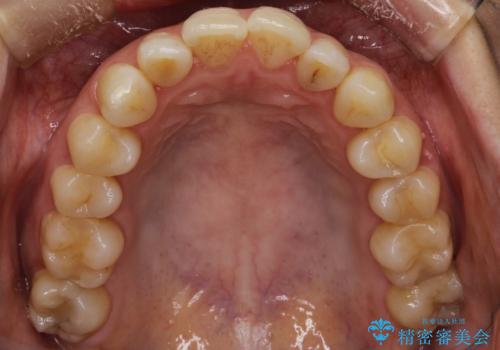

上顎の前歯が前方に傾斜して、下顎の前歯と接触していない状態でした。

上顎の前から4番目の歯を両側抜歯して前歯を後方に移動させる計画としました。

前歯がしっかり下がることで、上下の前歯があわさり食事もしやすくなったと言っていただきました。